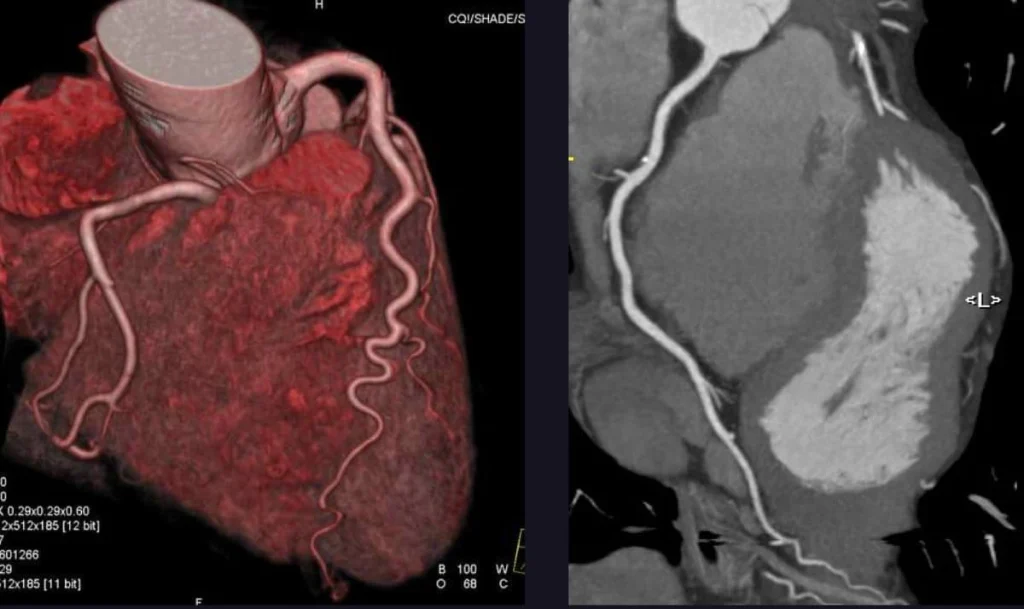

6. CT Coronary Angiography

Purpose: Non-invasive alternative to traditional coronary angiography.

CT coronary angiography uses advanced imaging techniques to visualize the coronary arteries and detect blockages.

Procedure:

- A contrast dye is injected through an IV.

- The patient undergoes a CT scan, which creates 3D images of the arteries.

Advantages:

- It is non-invasive and provides detailed images.

- Ideal for patients with low to intermediate risk.

Limitations: It may not be suitable for patients with irregular heart rhythms or significant calcium deposits.